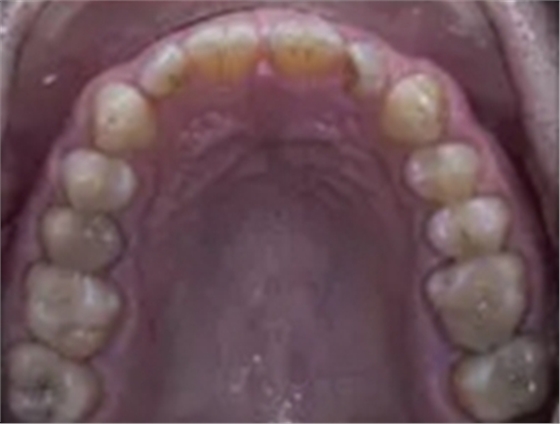

一位寻求改善微笑面容的43岁荷兰阿尔梅勒男子通过其全科牙医的介绍来到一家正畸医生的私人诊所,以纠正其错合畸形并在上颌前牙区域放置6个贴面。他属于牙形I类错合畸形,轻度骨性III类,覆合和覆盖减少以及前牙区存在间隙(图1)。

在最初的正畸咨询期间,拍摄了口内和口外照片连同一张全景片(图2),一张侧位头影片(图3)和正畸研究模型的海藻酸盐印模。